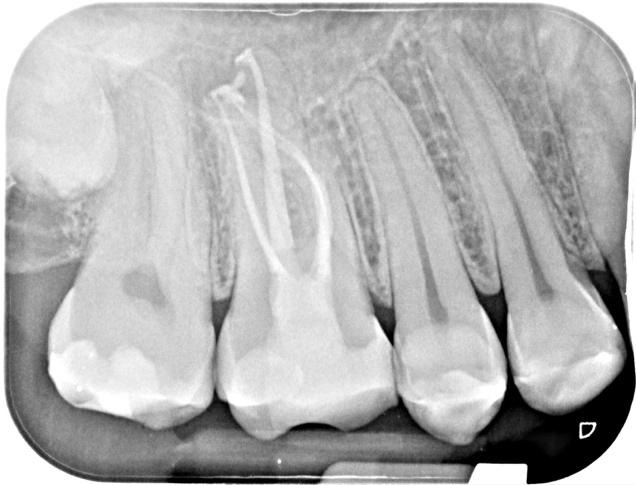

Obturated with

Hydraulic condensation with TotalFill BC sealer Hiflow

Follow-Up

Cuspal coverage planned for this tooth and a 1 year follow up has been made.